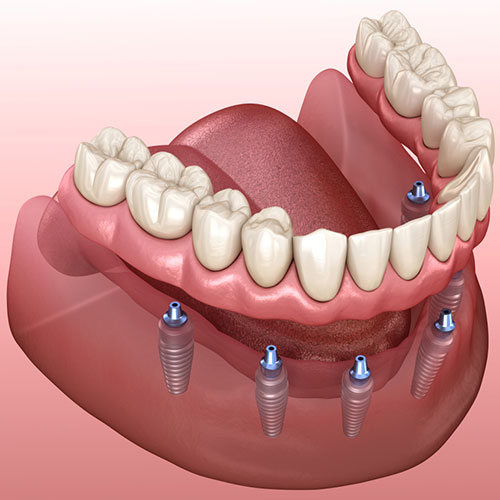

ایمپلنت های دندانی

ایمپلنت ها طبیعی ترین دندان هایی هستند که می توانند جایگزین دندان های از دست رفته شوند. ایمپلنت ها معمولا از جنس تیتانیوم ساخته می شوند و یک جایگزین موثر برای ریشه دندان به شمارمی روند. از آنجایی که ایمپلنت دندانی در استخوان فک قرار می گیرد ، با استخوان طبیعی فک فرد یکپارچه شده و به عنوان ، یک پایه محکم و با دوام برای پروتزهای دندانی شناخته می شود.

مهم ترین مزیت ایمپلنت های دندانی محکم بودن و یا دوام بودن آنهاست. همچنین ایمپلنت ها شکل طبیعی چهره و لبخند افراد را حفظ می کنند. ایمپلنت های دندانی به بهترین شیوه از سلامت استخوان فک حفاظت کرده و هیچ پوسیدگی ایجاد نمی کنند. علاوه بر تمامی این موارد ، ایمپلنت های از دندان های سالم فرد حفاظت و نگهداری می کنند.

بیشترین قسمت هزینه ایمپلنت های دندانی به موادی که برای ساخت ایمپلنت مورد استفاده قرار می گیرد و تعداد ایمپلنت ها بستگی دارد. سایر هزینه های درمانی با استفاده از ایمپلنت ها بسته به جراحی ، تجربه و تخصص دندانپزشک متغیر است.